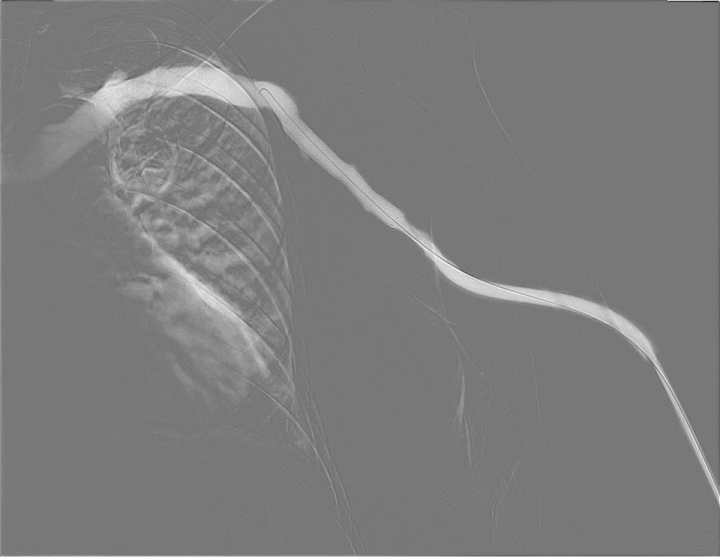

투석중 혈류 저하,

풍선확장술로 회복

시술 전

시술 후